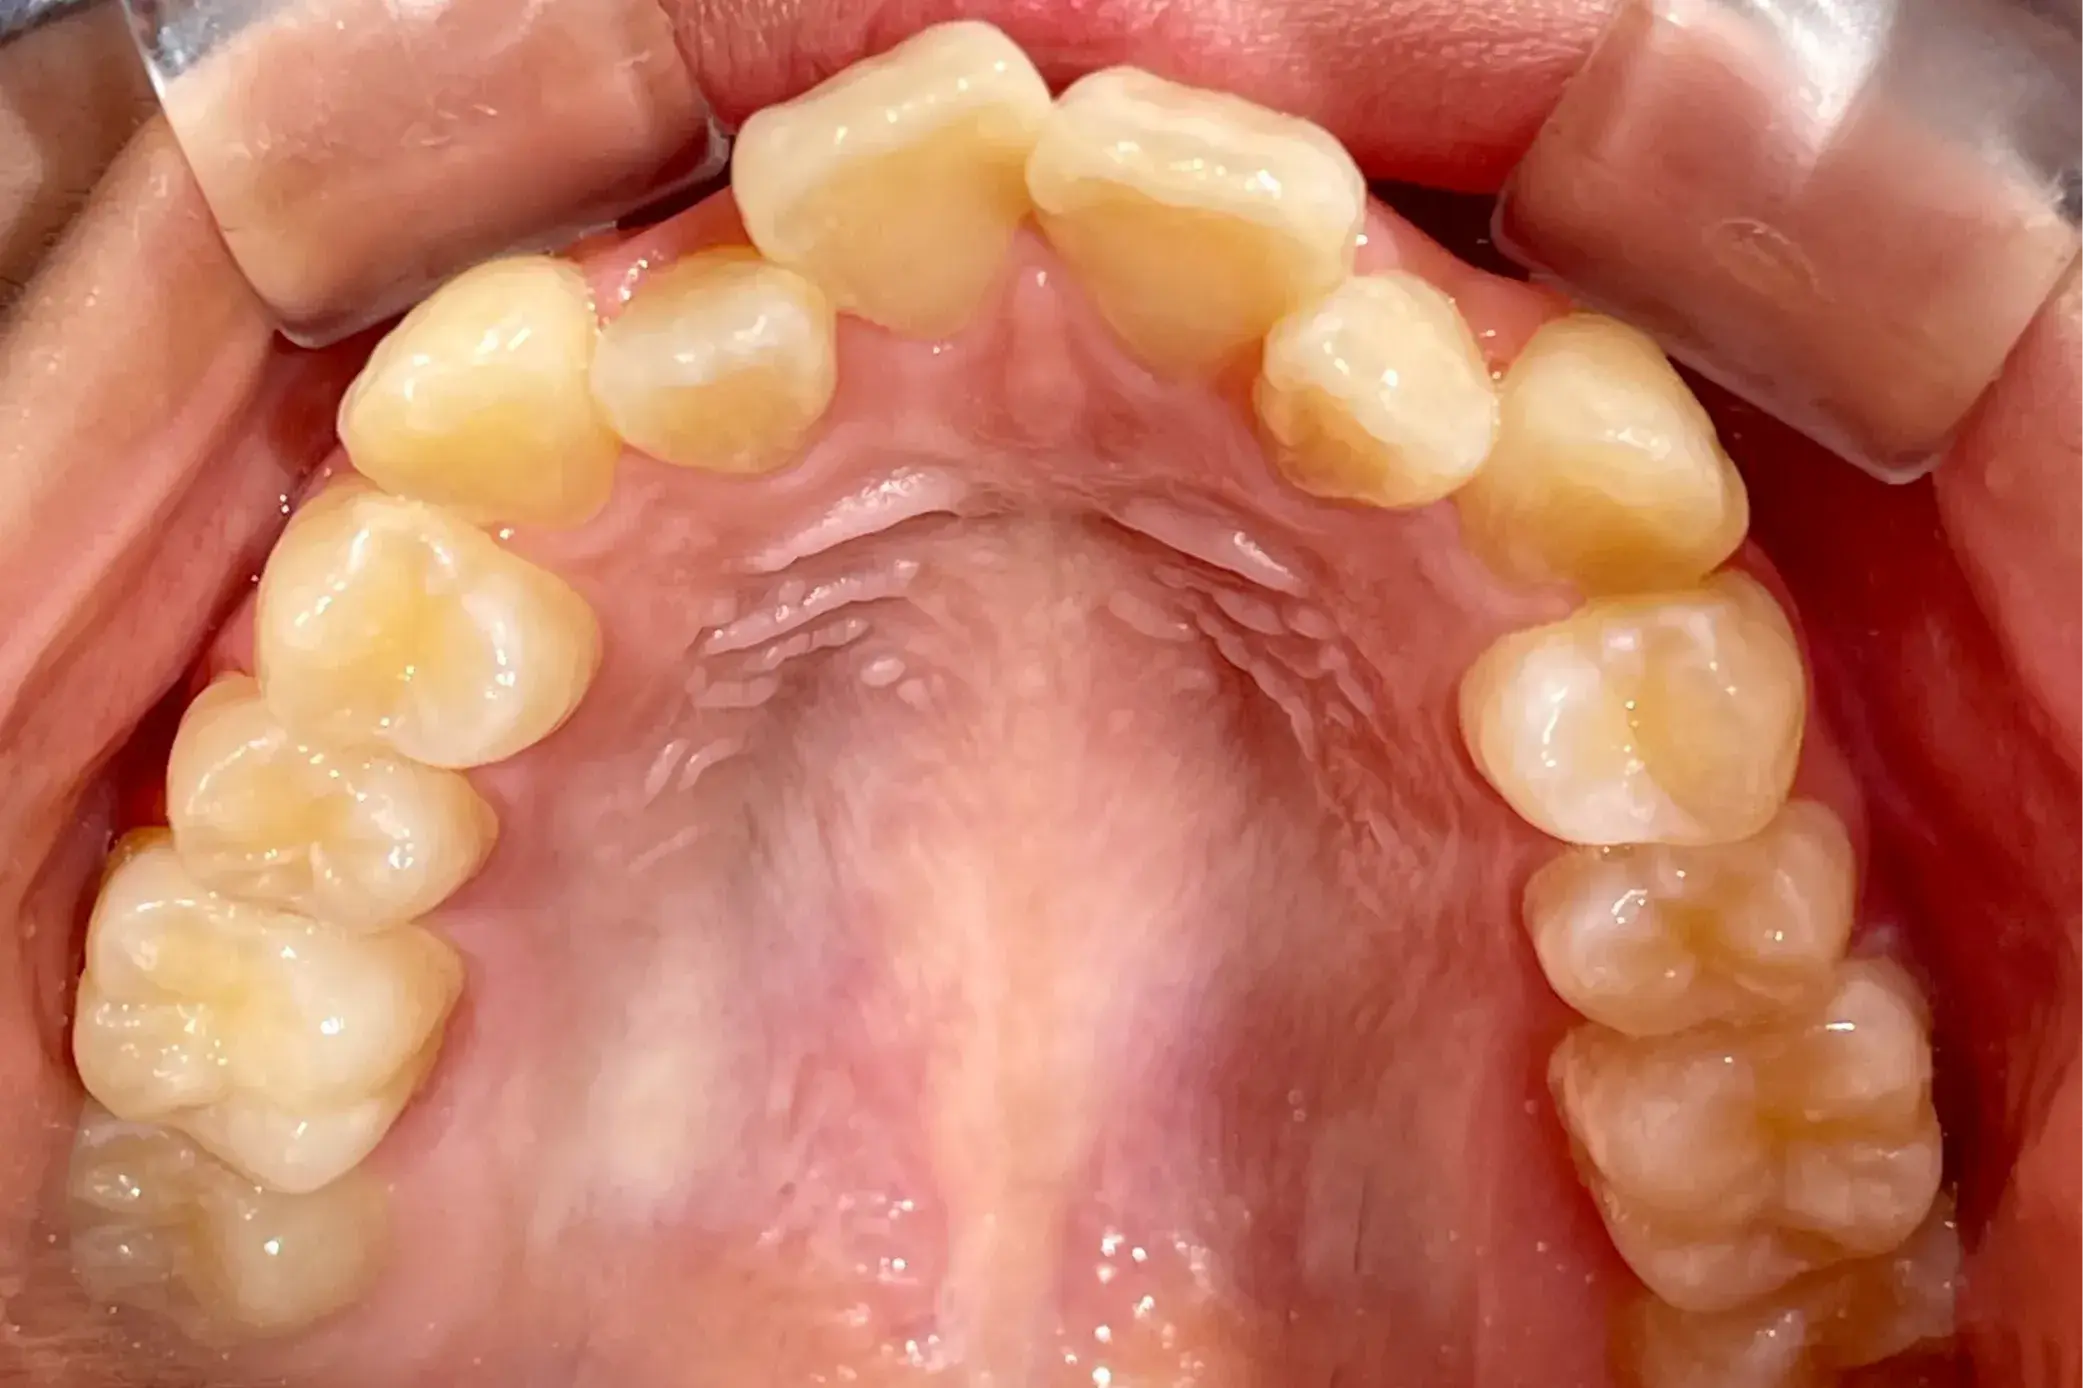

- 症例1

治療期間 4カ月

治療費 23.1万円(月額1,925円~)

※上顎前歯部、下顎前歯部の叢生をマウスピース型矯正装置で改善したケース。矯正治療上のリスクとして、治療中の虫歯、歯根吸収、歯肉炎 ・歯周炎の発生などが考えられる。